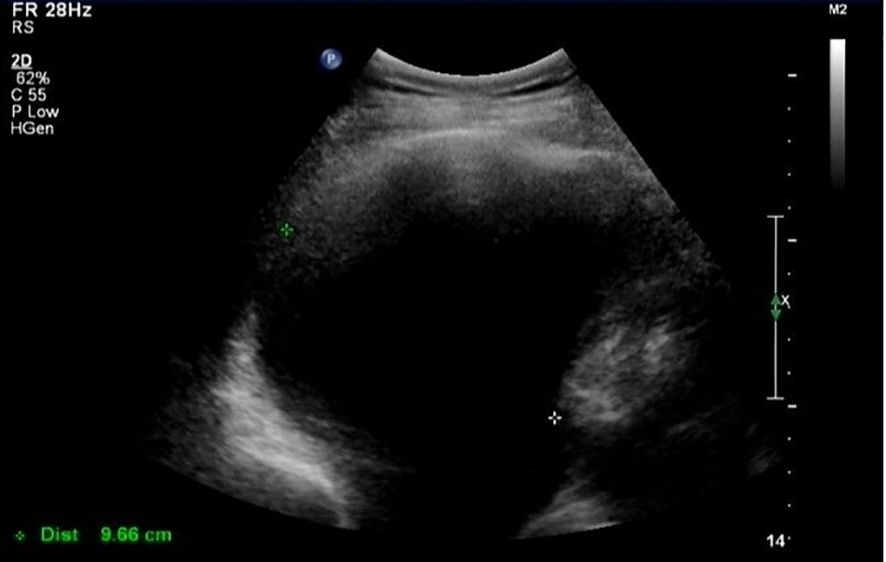

In March 2021 (3 months after the last chemotherapy), a hard mass that was approximately 5 cm in diameter on the left lower jaw was palpable. CA-125 was 1,863 U/mL. Ultrasound result showed a right pleural effusion (9.8 cm in depth, Figure 1). Thoracentesis was performed, and the drainage fluid had a milky white appearance (Figure 2). The laboratory analysis of the pleural fluid revealed exudative chylous fluid with triglyceride levels >1.24 mmol/L (110 mg/dL), a cholesterol level <5.18 mmol/L (200 mg/dL), and a positive chyle test. Cytological pathology revealed adenocarcinoma cells. The patient was diagnosed with platinum-resistant recurrence of ovarian cancer combined with right-sided chylothorax. Conservative treatment of chylothorax and chemotherapy for recurrent ovarian cancer were recommended by a multi-disciplinary team, including nutriology, respiratory oncology, thoracic surgery, and intervention departments. Surgery was not feasible because of disseminated multiple metastatic enlarged lymph nodes of ovarian cancer. Chylothorax was managed conservatively, including a strict diet with low-fat medium–long-chain triglycerides and chest tube insertion with interleukin-2 intrapleural perfusion (3 million units). Chylothorax improved significantly with progressively reduced and transparent pleural effusion (Figure 2). The drainage fluid was reduced to 50 mL/day on the fifth day, and then the drainage tube was removed. However, long-term intake of medium–long-chain triglycerides affected her quality of life negatively, and the patient was not able to adhere to the diet plan and gradually resumed the regular diet. Therefore, chylothorax recurred, and thoracentesis was performed repeatedly with IL-2 or cisplatinum pleural perfusion at intervals of 2–5 months (a total of six times). Chyle was produced slowly and did not affect the quality of life of the patient. Oral etoposide and bevacizumab were maintained from November 2021 to May 2022 (the patient refused PARP inhibitors due to economic reasons). The patient achieved a partial response (CA-125 91 U/L, lymph node reduction, and pleural fluid maintained at 3.1–5.8 cm).

Figure 1

Ultrasound image of pleural effusion.